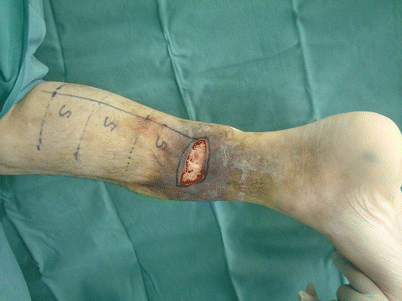

Fig. 16.8

Procedure 2: In prone position, the skin flap axis is established in the center of the posterior lower leg. The flap pivot point is set at 5 cm proximal from the lateral malleolus, and the skin flap is designed above the sural nerve and small saphenous vein (center of posterior lower leg) using the same distance as the distance from this point to the skin defect area